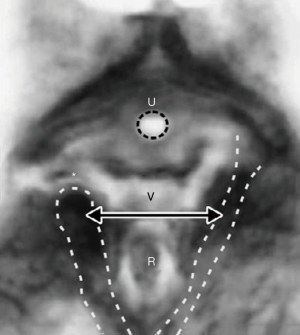

Как показано на рисунке 7, расширение влагалища при прохождении головки, даже в полностью согнутом положении (9,4 см), оказывает огромное давление на лобково-уретральную связку и мышцы тазового дна в местах их прикрепления к лону, вызывая стрессовое недержание мочи (СНМ) и смещение лобково-копчиковой/пуборектальной мышцы, прикрепляющихся к лону (10) (рисунок 8).

Как показано на рисунке 10, в круге "3" головка плода может чрезмерно растягивать крестцово-маточные связки, вызывая опущение матки и энтероцеле. Если латеральные отделы, за счет которых крестцово-маточная связка крепится к прямой кишке "R", тянут переднюю стенку прямой кишки вперед по мере удлинения крестцово-маточной связки, передняя стенка прямой кишки может растягиваться вперед, вызывая инвагинацию прямой кишки (11) (рис. 11), которая может быть устранена с помощью восстановления крестцово-маточной связки (12); на круге "2" удлинение или разрыв кардинальной связки может привести к цистоцеле (поперечному дефекту); в круге "4" повреждение промежности может привести к ректоцеле и синдрому низкой промежности; в круге "1" избыточное давление на мышцу, поднимающую задний проход, может привести к смещению или разрыву их коллагеновых вставок в лобковом симфизе, в то время как избыточное давление на лобково-уретральную связку может привести к СНМ.